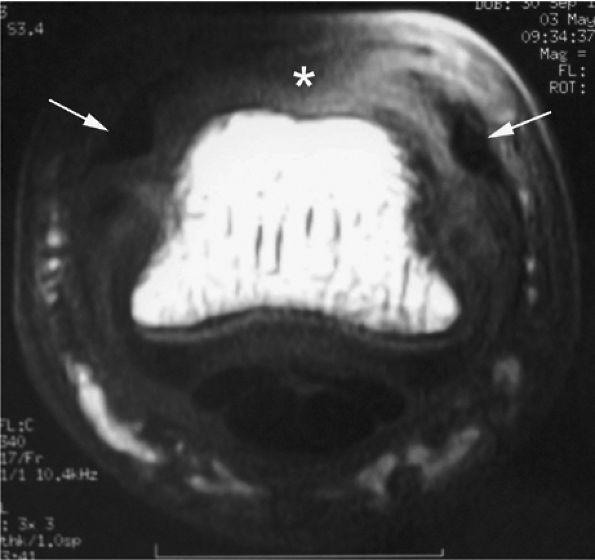

FIGURE 11.43 ● Acute open injury of the flexor pollicis longus tendon. (A) On these coronal post-contrast fat-suppressed T1-weighted images, the distal end of the tendon can be seen at the entry of the digital canal (arrows). (B) The proximal end is seen at the level of the radiocarpal joint (arrows). The tendon gap measures 6 cm. The empty tendon sheath shows significant synovitis (arrowheads in both images).

|